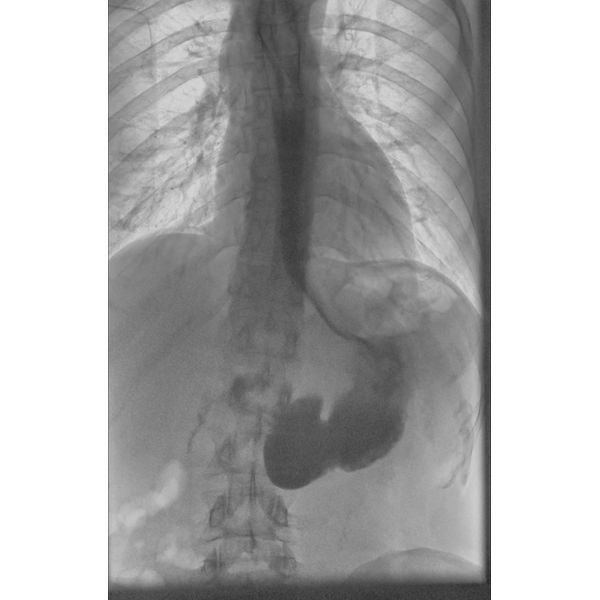

В ходе рентгеноскопии пищевода и желудка с контрастным веществом выявлено, что дистальный отдел пищевода (нижняя часть, примыкающая к желудку) сужен по типу хвоста мыши, что указывает на ахалазию кардии (нарушение работы клапана между пищеводом и желудком). Над этим участком пищевод умеренно расширен без S-образной деформации, т. е. он не удлинился и не искривился.